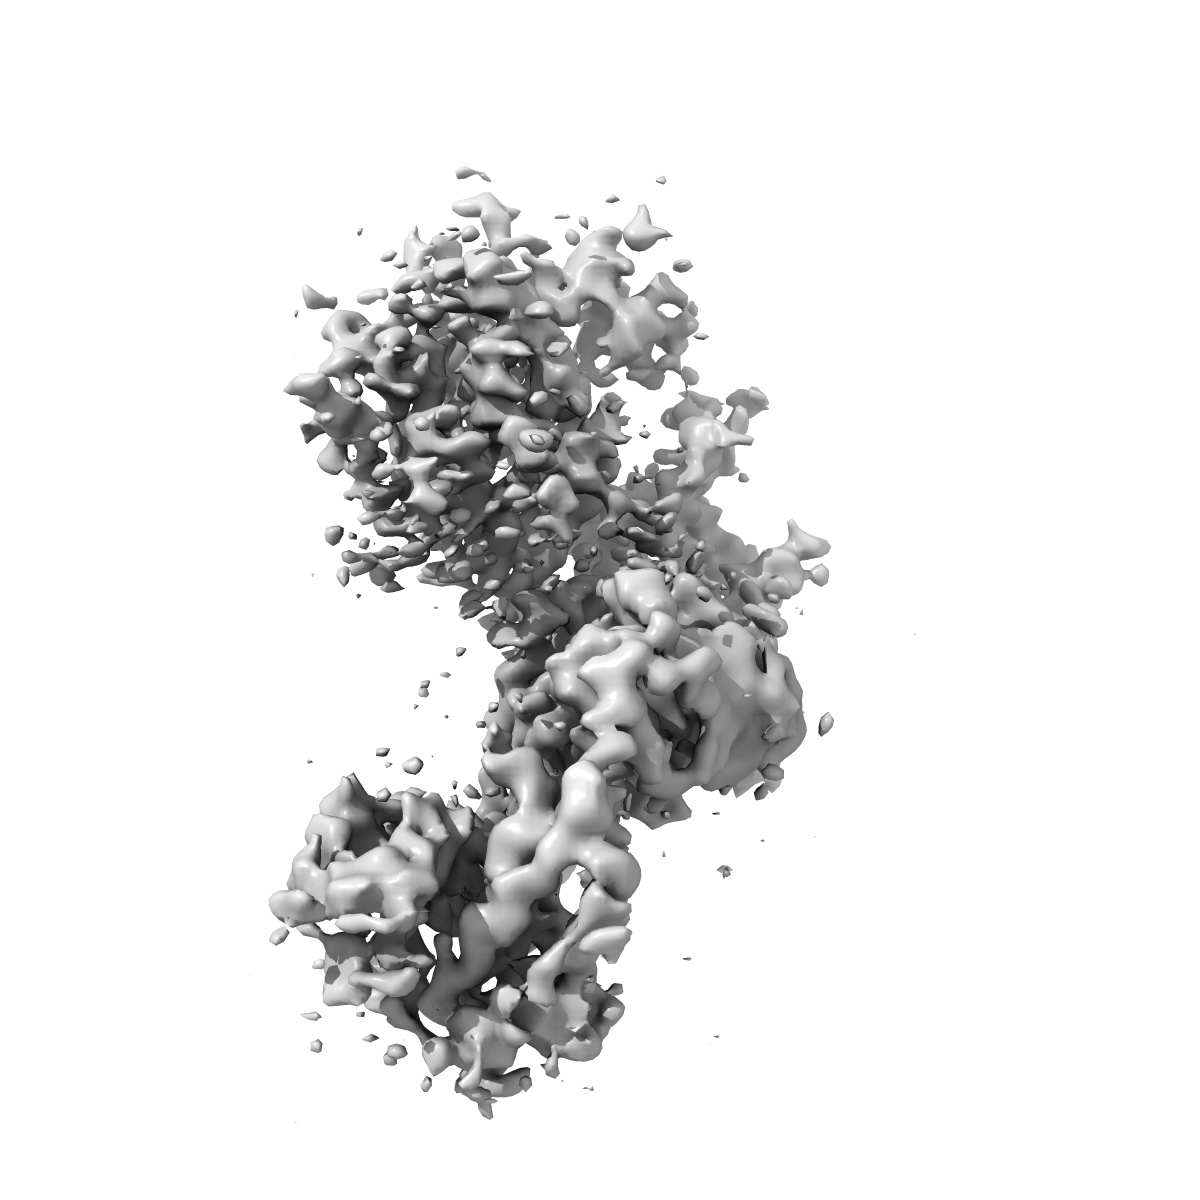

SARS-CoV-2 Spike (2P) in complex with G32R7 Fab (RBD and NTD local reconstruction)

Sample: SARS-CoV-2 Spike in complex with G32R7 Fab

Fitted models: 7n64

Deposition Authors: Windsor IW, Tong P

Memory B cell repertoire for recognition of evolving SARS-CoV-2 spike.